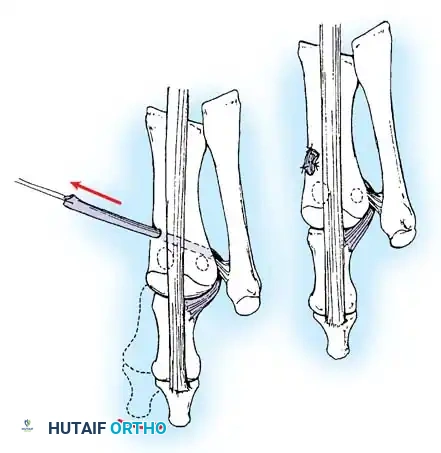

• Using a Freer elevator or a small osteotome for its strength, mobilize the fi bular sesamoid (Fig. 78-31A to C). This may be diffi cult in elderly patients with signifi cant deformity and adherence of the sesamoid to the metatarsal head. Lift the metatarsal dorsally for exposure (Fig. 78-31D and E).

• When the sesamoid has been removed, insert two 0.062-inch Kirschner wires retrograde from the tip of the toe 2 to 3 mm plantar to the nail bed, leaving about 5 to 7 mm of the pins exposed at the base of the phalangeal remnant to help align the phalanx on the metatarsal before antegrade passage of the pins into the metatarsal (Fig. 78-31F).

LATERAL DISPLACEMENT OF THE FIRST METATARSAL

Fig. 78-31 Excision of fi bular sesamoid in modifi ed Keller procedure. With base of proximal phalanx removed and medial eminence excision, exposure of fi bular sesamoid is not as diffi cult from medial incision. A, Operative photograph showing elevation of fi rst metatarsal with strong two-tooth retractor and use of small osteotome to mobilize fi bular sesamoid and lateral capsuloligamentous (frequently contracted) structures. Osteotome is between metatarsal head and lateral sesamoid. When mobilization of fi bular sesamoid is complete, entire sesamoid is visible for excision. Note chondromalacia of tibial sesamoid articular surface medial to osteotome. B, Fibular sesamoid has been excised, and lateral capsular structures and conjoined tendon (in forceps) have been released. Neurovascular bundle to lateral side of hallux is adjacent to these structures. C, Diagrammatic representation of modifi ed Keller procedure. By excising fi bular sesamoid, valgus moment of conjoined tendon of fl exor hallucis brevis and adductor hallucis no longer pulls fl exor hallucis longus tendon laterally (carrying hallux with it) through capsulosesamoid plantar plate and pulley system. D, Metatarsal head must be lifted dorsally to excise fi bular sesamoid under direct vision. E, Note exposure of fi bular sesamoid after mobilization of metatarsal head. Continued

F G

Fig. 78-31, cont’d F, Two 0.062-inch Kirschner wires are drilled distally. G, First metatarsal head is manually displaced laterally, and hallux is placed end-on the fi rst metatarsal. Kirschner wires are drilled proximally across joint. H, Capsule is mobilized dorsally and plantarward. I, 2-0 or 3-0 absorbable sutures placed in purse-string fashion are used for capsular closure. J, Capsule must be closed over joint. Note pins cut off at skin level; they also can be bent at skin level.